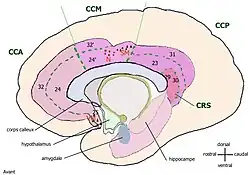

Les deux divisions principales sont classiquement désignées [3] :

- le cortex cingulaire antérieur CCA, qui consiste dans les aires de Brodmann 24 et 25,

- le cortex cingulaire postérieur CCP, qui consiste dans les aires de Brodman 29, 30, 23, et 31, assure des fonctions « évaluatives ». Parfois la région retrospleniale formée des aires 29 et 30 est considérée à part.

Vogt[4] (1993) a proposé une nouvelle division en quatre parties :

- le cortex cingulaire antérieur, CCA

- le cortex cingulaire moyen, CCM

- le cortex cingulaire retrosplenial, CRS

- le cortex cingulaire postérieur, CCP

On peut diviser le gyrus cingulaire en quatre grandes parties, chacune d'elles accomplissant des tâches spécifiques. Le cortex cingulaire antérieur (CCA) occupe ainsi un rôle dans les états affectifs alors que le cortex cingulaire moyen (CCM) intervient dans le choix des réponses. Le cortex cingulaire postérieur (CCP), quant à lui, tient une place dans la fonction mémorielle. Enfin, le cortex cingulaire rétrospinal (CCR), participe au traitement des informations visuo-spatiales.

L'ancien "cortex cingulaire antérieur" est maintenant divisé en cortex cingulaire antérieur et moyen et l'ancien "cortex cingulaire postérieur", maintenant nommé gyrus cingulaire postérieur est divisé en cortex cingulaire postérieur et retrosplenial.

Certains chercheurs continuent à utiliser la division bipartie mais la plupart ont adopté la division quadripartie, aux risques de confusion entre les valeurs ancienne et nouvelle de CCA et CCP.

Vogt résume les corrélations fonctionnelles des quatre régions cingulaires ainsi :

- le CCA périgénual est impliqué dans les affects

- le CCM dans la sélection des réponses

- le CCP dans le traitement visuo-spatial

- le CRS dans l'accès aux souvenirs